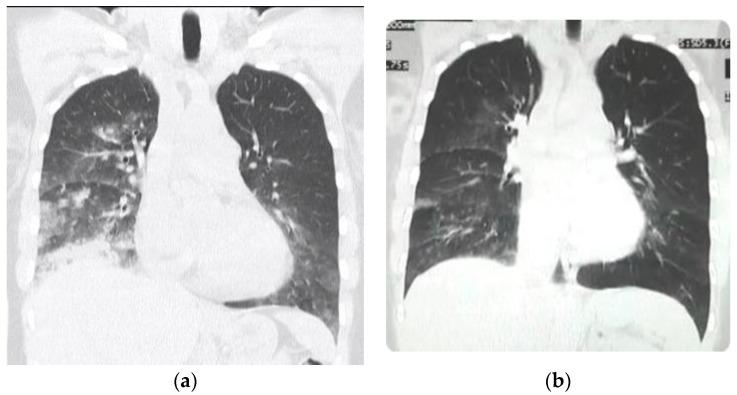

Acute high-altitude illnesses are of great concern for physicians and people traveling to high altitude. Our recent article "Acute Mountain Sickness, High-Altitude Pulmonary Edema and High-Altitude Cerebral Edema, a View from the High Andes" was questioned by some sea-level high-altitude experts. As a result of this, we answer some observations and further explain our opinion on these diseases. High-Altitude Pulmonary Edema (HAPE) can be better understood through the Oxygen Transport Triad, which involves the pneumo-dynamic pump (ventilation), the hemo-dynamic pump (heart and circulation), and hemoglobin. The two pumps are the first physiologic response upon initial exposure to hypobaric hypoxia. Hemoglobin is the balancing energy-saving time-evolving equilibrating factor. The acid-base balance must be adequately interpreted using the high-altitude Van Slyke correction factors. Pulse-oximetry measurements during breath-holding at high altitude allow for the evaluation of high altitude diseases. The Tolerance to Hypoxia Formula shows that, paradoxically, the higher the altitude, the more tolerance to hypoxia. In order to survive, all organisms adapt physiologically and optimally to the high-altitude environment, and there cannot be any "loss of adaptation". A favorable evolution in HAPE and pulmonary hypertension can result from the oxygen treatment along with other measures.

急性高原病是医生和前往高原地区的人们非常关注的问题。我们最近的一篇文章“急性高原病、高原肺水肿和高原脑水肿,来自高海拔安第斯山脉的观点”受到了一些海平面高海拔专家的质疑。因此,我们对一些观察结果进行了回答,并进一步解释了我们对这些疾病的看法。高原肺水肿 (HAPE) 可以通过氧运输三联体更好地理解,该三联体涉及气动泵(通气)、血液动力学泵(心脏和循环)和血红蛋白。这两个泵是初次暴露于低压缺氧时的第一个生理反应。血红蛋白是平衡节能时间演变的平衡因素。必须使用高海拔范斯莱克校正因子充分解释酸碱平衡。在高海拔屏息期间进行脉搏血氧仪测量可评估高原疾病。缺氧耐受公式表明,矛盾的是,海拔越高,对缺氧的耐受能力越强。为了生存,所有生物都在生理上和最佳地适应高海拔环境,不会有任何“适应丧失”。通过氧疗和其他措施,可以使 HAPE 和肺动脉高压得到有利的进化。

Morphological and functional findings in COVID-19 lung disease as compared to Pneumonia, ARDS, and High-Altitude Pulmonary Edema.与肺炎、ARDS 和高原肺水肿相比,COVID-19 肺部疾病的形态和功能研究结果。

Respir Physiol Neurobiol. 2023 Mar;309:104000. doi: 10.1016/j.resp.2022.104000. Epub 2022 Nov 29.